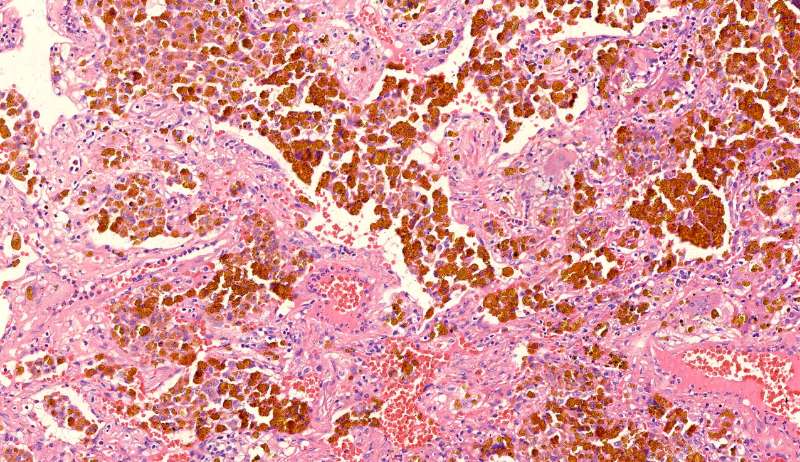

这些就是隐球菌,常被巨噬细胞吞噬,大多为多核巨噬细胞 隐球菌感染,在免疫力正常情况下,就是个肉芽肿 小白球,略显淡蓝色,这是荚膜的感觉

隐球菌在HE染色是小白球,隐隐的,球状的。在PAS染色是红色的小球,在六铵银染色是黑褐色的小球。

整体是个类圆形,边界模糊(有晕征的感觉),肉芽肿一般都这样 里面也能见到许多小白球,大小从3微米到20微米不等 红细胞直径5-6微米 普通小淋巴细胞直径5微米 这里淋巴细胞挺多 有许多淋巴细胞,成堆

多核巨噬细胞吞了许多隐球菌 经常是反包围的感觉

这三幅是周围区,也有巨噬细胞,单核的多 都在肺泡腔内 所以有ggo样密度 过一段时间,晕就消失,有时是消退,有时是实性区扩大,盖住磨玻璃晕 那也是吞噬的作用,常代表免疫力正常 就是警察多了把肺泡填了